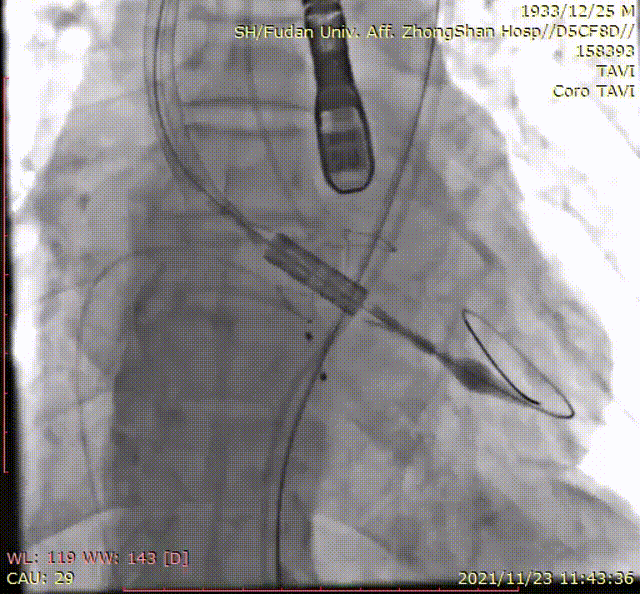

手术过程

输送系统到位

定位环释放

瓣膜精准定位

本例临床试验的患者是一例单纯性重度主动脉瓣关闭不全患者。在手术过程中,这款瓣膜产品使用体验非常流畅,仅仅31分钟就完成了手术。